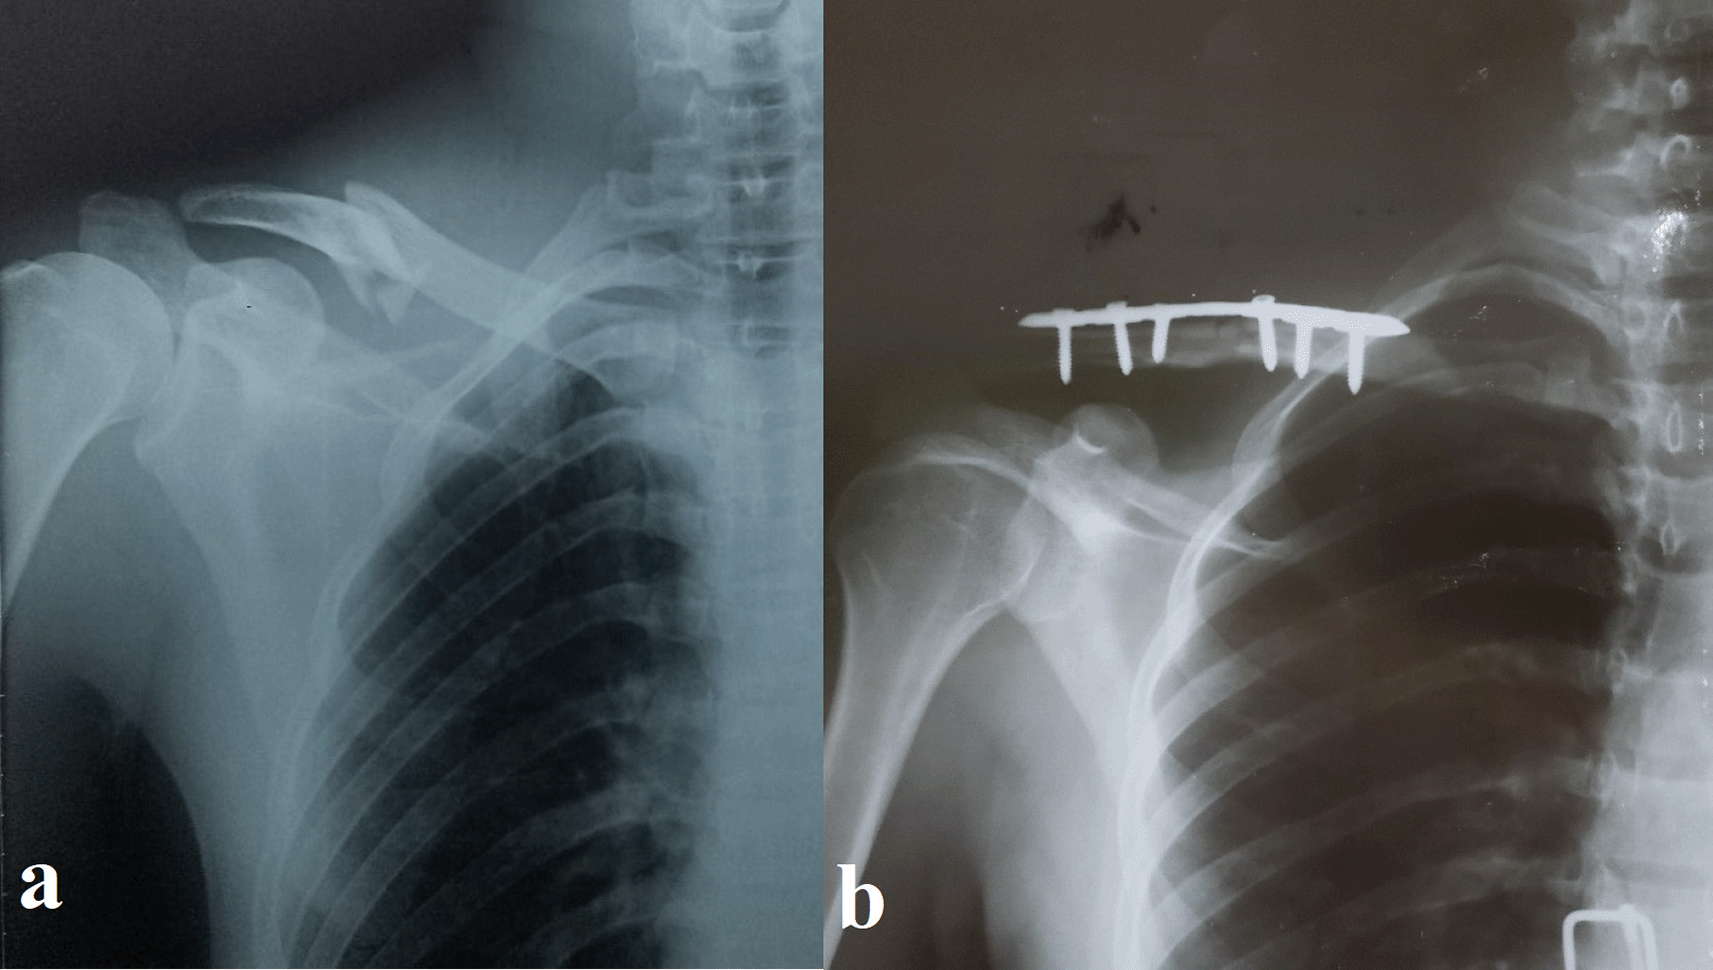

Sixty-five patients with displaced midshaft clavicular fractures treated with precontoured locked plates were enrolled. The mean age was 32.09 years (range: 19–50 years), with 54 males (83.1%) and 11 females (16.9%). Road traffic accidents (RTAs) caused the most injuries (n=43, 66.2%), followed by falls (n=22, 33.8%). The right clavicle was affected in 43 (66.2%) patients and the left clavicle in 22 (33.8%). Table 1 details these traits, and Figures 1–2 show representative cases.

(a) Preoperative anteroposterior radiograph showing a displaced, slightly comminuted midshaft fracture of the right clavicle in a 30-year-old male patient. (b) Postoperative anteroposterior radiograph of the same patient following open reduction and internal fixation (ORIF) with a pre-contoured superior locking plate (Orthomed E, 7-hole, titanium). Note the anatomical reduction of the fracture and the use of locking screws that engage at least four cortices on either side of the fracture.